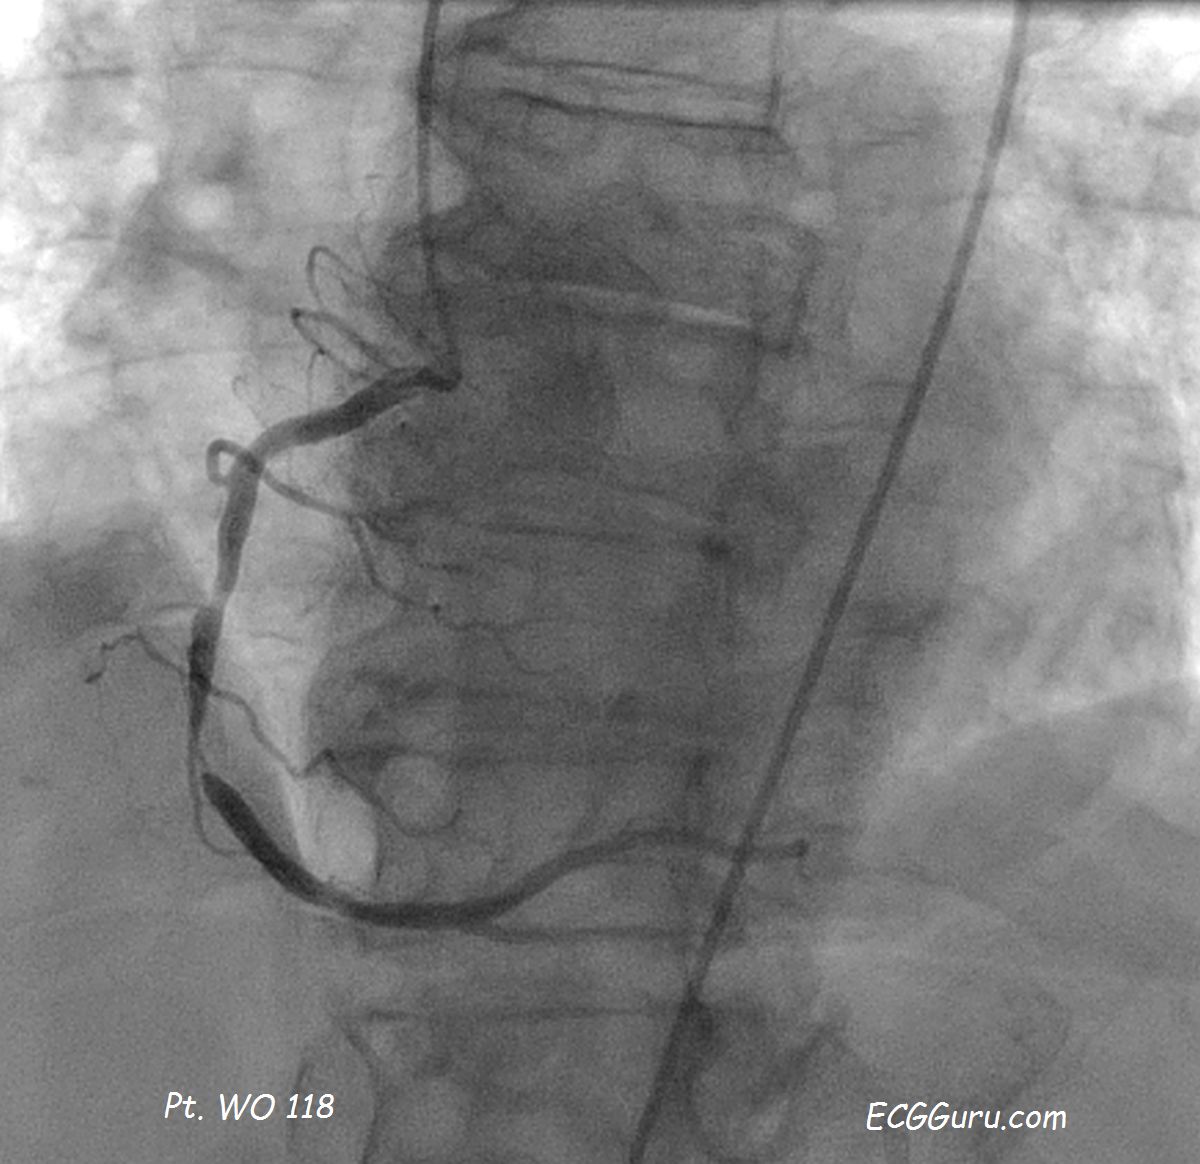

Right Coronary Artery with severe disease